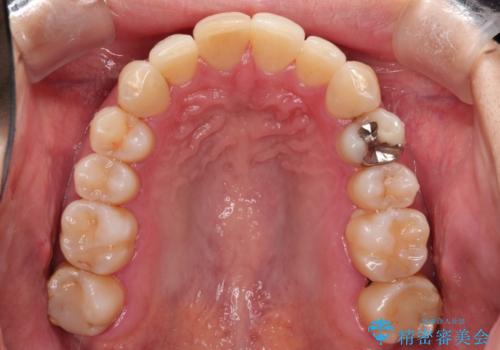

- 以前矯正をしていたが、わずかに後戻りをしてしまったのを主訴に来院されました。

装置はなるべくつけたくないとのことで、インビザラインにて治療することとなりました。